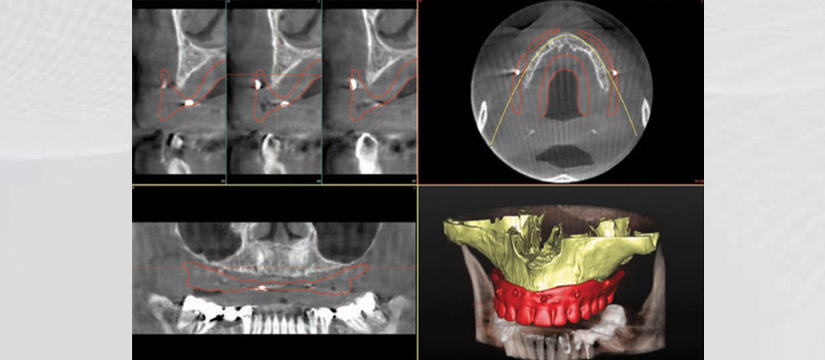

Klinika jonë premton se do t’ju ofrojë gjithnjë cilësinë më të lartë të shërbimit, me fjalën më të fundit të teknologjisë. Së fundmi ne jemi pajisur me pajisjen OWANDY IMAX TOUCH 3D. Kjo pajisje siguron me thjeshtësi dhe efikasitet imazhe high-definition për një diagnostikim të pagabueshëm. OWANDY është lideri i prodhimit të pajisjeve radiografike dentare në Francë, Amerikë, Gjermani e më gjerë. Produkti më i ri i OWANDY I-Max Touch 3D siguron të gjitha shërbimet radiografike në një aparaturë të vetme.

Aparatura posedon 17 programe të ndryshme ku mund të behën incizime si:

- 3D Dentare

- 3D Pozicioni i sinusit